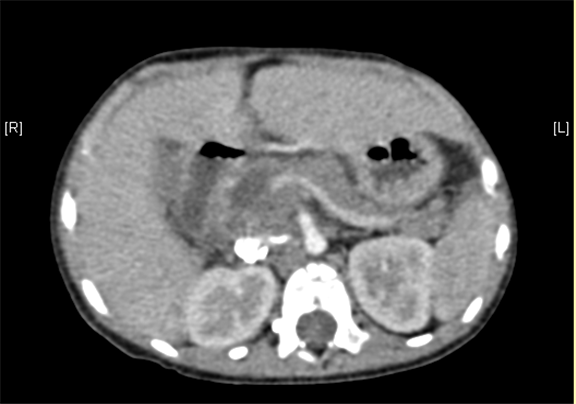

术后CT检查:

动脉期

静脉期

平衡期

术后病理提示肾母细胞瘤(上皮型)

术后给予抗炎、补液、止血等对症支持治疗。患儿恢复良好,无腹痛,伤口愈合好,无渗血渗液,于2016-2-14出院。